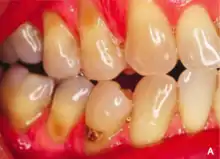

Abrasion is the non-carious, mechanical wears of tooth from interaction with objects other than tooth-tooth contact.[1] It most commonly affects the premolars and canines, usually along the cervical margins.[2] Based on clinical surveys, studies have shown that abrasion is the most common but not the sole aetiological factor for development of non-carious cervical lesions (NCCL) and is most frequently caused by incorrect toothbrushing technique.[3]

Abrasion frequently presents at the cemento-enamel junction and can be caused by many contributing factors, all with the ability to affect the tooth surface in varying degrees.[4]

The appearance may vary depending on the cause of abrasion, however most commonly presents in a V-shaped caused by excessive lateral pressure whilst tooth-brushing. The surface is shiny rather than carious, and sometimes the ridge is deep enough to see the pulp chamber within the tooth itself.

With the presence of non-carious cervical loss due to abrasion, this may lead to consequences and symptoms such as increased tooth sensitivity to hot and cold, increased plaque trapping which will result in caries and periodontal disease, difficulty of dental appliances such as retainer and denture in engaging the tooth, and also it may be aesthetically unpleasant to some people.[3]